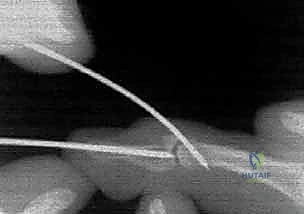

- Pulley System: The FDP tendon is secured by a series of annular (A) and cruciate (C) pulleys. At the level of the DIP joint, the A4 and A5 pulleys are particularly relevant, along with the C3 cruciate pulley. Preservation of these pulleys is paramount during any surgical approach to prevent bowstringing of the tendon.

- Vascular Supply (Vinculae): The FDP receives its blood supply via the vinculum longus profundus and vinculum brevis profundus, thin mesenteries that attach the tendon to the flexor sheath. These are critical for tendon viability, especially in avulsion injuries. Type I FDP avulsions, which retract into the palm, often disrupt these vinculae, leading to poor blood supply and demanding urgent intervention.

* Surgeon's Directive: "Now we expose the flexor tendon sheath. Remember our pulley system: A2, A3, A4, A5. We must preserve the A2 and A4 pulleys, as they are crucial for preventing FDP bowstringing and maintaining efficient finger flexion. I'm carefully incising the C1, A3, and C2 pulleys to gain access to the FDP tendon, but leaving A2 and A4 intact."

7. Tendon Reattachment (Pure Tendinous Avulsion):

* Surgeon's Directive: "If this were a pure tendinous avulsion, we would use a different approach. We'd prepare a bone tunnel or use suture anchors. For a bone tunnel, I'd drill two small tunnels from the dorsal aspect of the distal phalanx, exiting volarly at the FDP insertion site. We'd then pass sutures (e.g., modified Kessler or Bunnell) through the FDP tendon stump and then through these bone tunnels, tying them over a button on the dorsal aspect of the nail to create a secure pull-out repair. Alternatively, two small suture anchors can be placed directly into the volar base of the distal phalanx, and the FDP tendon is sutured to these anchors."

* Surgeon's Directive: "If any of the critical pulleys (A2, A4) were inadvertently damaged or had to be partially released for access, we must repair them. Use fine non-absorbable sutures (e.g., 5-0 Prolene) to reconstruct the pulley integrity. This is crucial to prevent bowstringing and maintain mechanical advantage for the FDP."